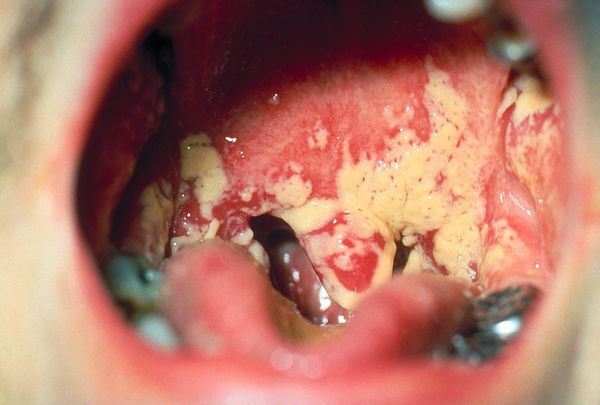

- Недавние глобальные оценки обнаружили следующее ежегодное проявление: 3 000 000 случаев хронического легочного аспергиллеза; 223 100 случаев криптококкового менингита, осложняющего ВИЧ/СПИД; 700 000 случаев инвазивного кандидоза, например, оральной молочницы, см. изображение 3 R; 250 000 случаев инвазивного аспергиллеза; 100 000 случаев диссеминированного гистоплазмоза; более 10 000 000 случаев грибковой астмы; 1 000 000 случаев грибковогокератита.[1]

- Candida albicans (обычно локализованная инфекция, например влагалища или слизистых оболочек рта)